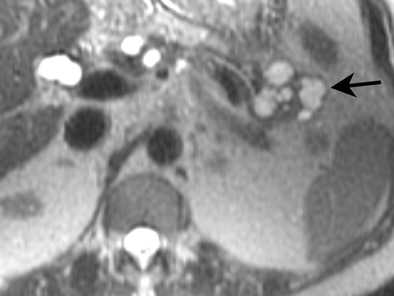

![]() |

| MRI demonstrating mucinous cystadenoma in tail of pancreas (arrow). On T2-weighted images the cyst fluid has high signal intensity similar to CSF. |